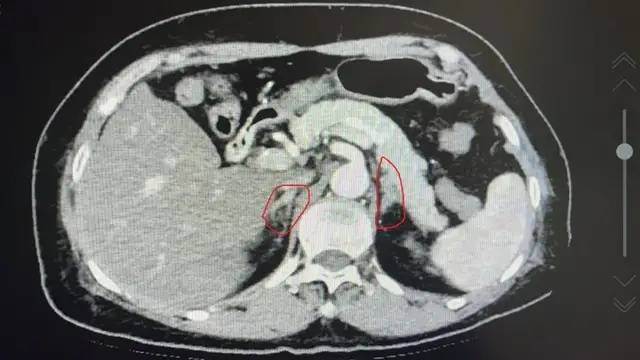

在完善一系列继发性高血压的相关检查后 , 原发性醛固酮增多症诊断明确 , 肾上腺增强CT显示 , 双侧肾上腺增厚 , 左侧肾上腺腺瘤 。